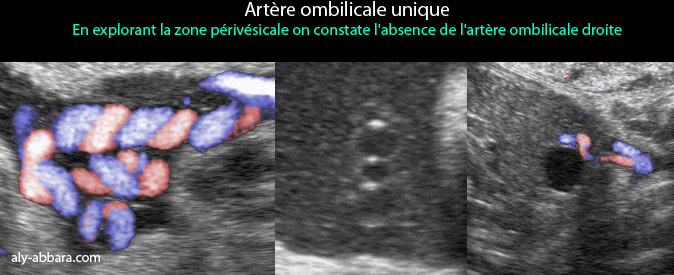

Le diagnostic échographique est possible par la réalisation d'une coupe transversale sur le cordon ; l'utilisation du Doppler couleur facilite ce diagnostic. Pour déterminer le côté de l'artère absente, il faut réaliser une coupe transversale au niveau de la vessie, sur cette coupe, le Doppler couleur met en évidence l'artère ombilicale manquante.